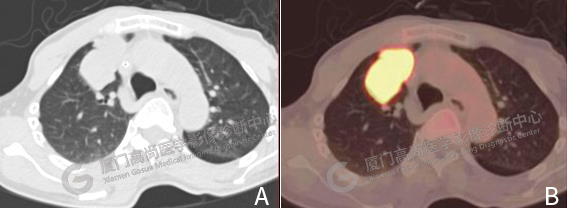

圖1: A 胸部CT圖像,右肺上葉前段軟組織腫塊,邊界清,形態(tài)不規(guī)則,邊緣分葉。B PET/CT胸部融合圖像,F(xiàn)DG代謝明顯增高。

右肺上葉前段軟組織腫塊,大小約5.2×3.2cm,邊界清,形態(tài)不規(guī)則,邊緣分葉,F(xiàn)DG攝取明顯增高,SUVmax 14.7(圖1)。